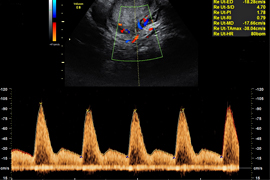

Dopplersonographie

Blutflussmessung

Bei der Dopplersonographie werden Blutgefäße dargestellt und die Strömungsgeschwindigkeit des Blutes gemessen. So können die zuführenden mütterlichen Gefäße (Gebärmutterarterien) und die kindlichen Gefäße (z.B. Nabelschnurarterien, Hirnarterien, Venen) untersucht werden. Hierdurch ist es einerseits möglich, eine Risikobewertung für eine Wachstumsstörung beim Kind oder für die Entwicklung mütterlicher schwangerschaftsbedingter Erkrankungen vorzunehmen. Andererseits kann das kindliche Wohlergehen bei Auffälligkeiten sehr zuverlässig bestätigt und überwacht werden.